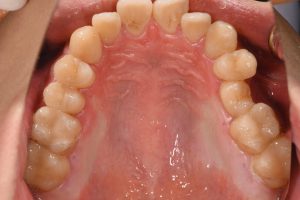

治療前

完成したセラミックインレー